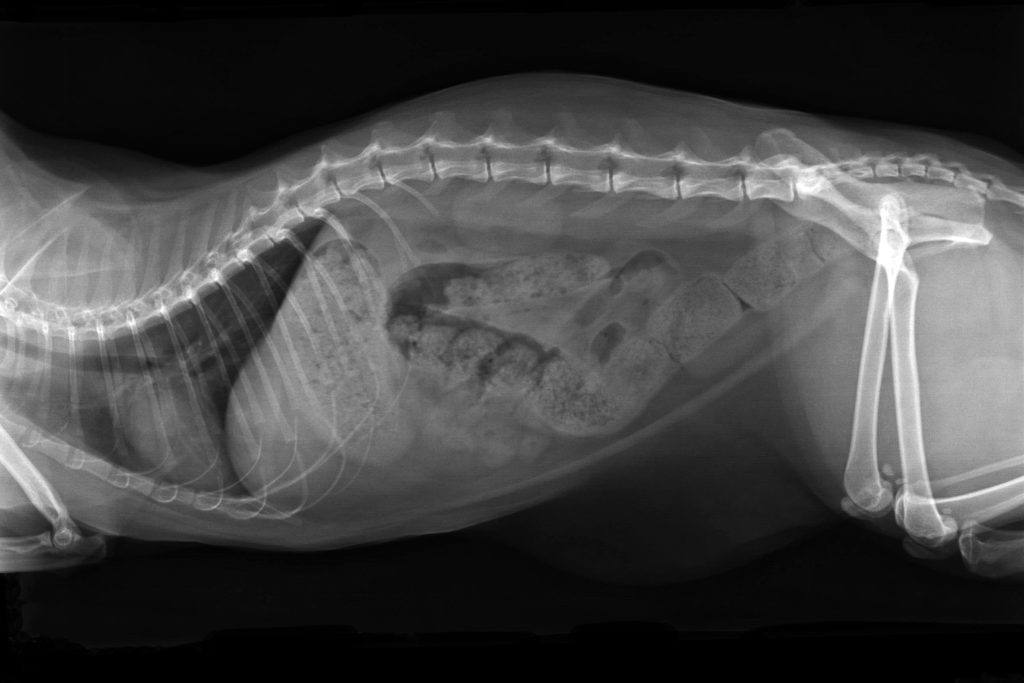

*= Radiografía de un gato con sobrepeso y obstrucción intestinal completa. Vista lateral.

Una larga lista… eso da que pensar, ¿no? Pero eso no es todo: el sistema inmunitario de los gatos con sobrepeso está debilitado, lo que hace que los gatos gordos sean más susceptibles de padecer enfermedades y dolencias graves. Y si luego hay que hacer una intervención o una operación, los gatos obesos también están entre los “pacientes de riesgo”.